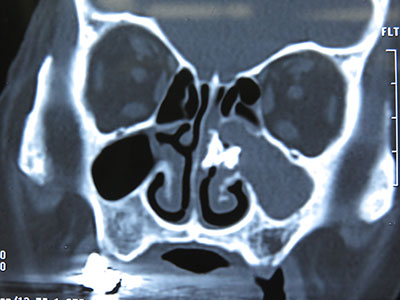

图一:鼻窦CT 所示

患者,女性,64岁,主诉左侧鼻腔涕中带血2-3月,伴左侧鼻塞不适,嗅觉可,偶尔头痛,无面部麻木、压痛、张口受限等症,饮食及睡眠正常,大小便正常,体重无明显变化。体格检查:一般情况好,鼻外形正常,鼻中隔略右偏,鼻腔粘膜干燥暗红,左侧中鼻道可见大量血痂,触之易出血,中鼻道具体结构无法窥清。鼻窦CT示:左侧中鼻道可见异常密度增高影,形态不规则(图1、2)。患者入院后在全麻下实施了鼻内镜下左侧鼻石取出术。术中见左侧鼻腔中鼻道一直径约1.5cm大小形态不规则的黑色鼻腔异物(图3),硬如石块,轻柔取出,中鼻道粘膜充血糜烂伴肉芽组织增生,取部分肉芽组织送病理,开放并扩大左侧上颌窦口。术毕左侧鼻腔填塞可吸收性纳吸绵及止血纱布,手术过程顺利。术后予抗炎消肿治疗,患者恢复平稳,顺利出院。术后1月电话随访患者无左侧鼻腔出血及头痛不适,鼻通气顺畅,感觉良好。病理回报慢性炎症。

讨论:鼻石,也叫鼻石病或鼻石症,是矿物盐类在鼻腔异物周围经数年的沉积而形成的块状物。鼻石是一种鼻腔少见病,多发生于一侧鼻腔,病程可长达数年。有学者认为在鼻腔异物的基础上,炎性渗出物包裹异物、鼻腔分泌物分解出多种无机盐沉积而逐渐形成,其成分主要为磷酸钙、氯化钠等。鼻石分为真性和假性,以后者多见。以外源性异物为核心称假性鼻石,包括纽扣、纸团、石块、水果核、豌豆、寄生虫、木棒、玻璃、纱布等;以内源性物质为核心称真性鼻石,包括细菌、干痂、坏死上皮、凝血块、碎骨片、牙齿等。典型的鼻石诊断主要靠鼻内镜检查,鼻窦CT检查可提高本病的确诊率。本例在CT表现为均匀致密的高密度影,与鼻腔粘膜形成鲜明对比,鼻石应与鼻异物及鼻腔牙相鉴别,前者有明确的异物塞入鼻腔病史,一般病程短,与周围组织无联系;后者为鼻底部白色突起的硬物,不易推动,X线片示高密度影,其根在鼻部骨质内。鼻石的治疗建议在鼻内镜下取出,一般预后良好,小的鼻石可在门诊局麻取出,较大较多的鼻石建议全麻下取出。本例鼻石较大,采取全麻取出,视野好,术中损伤小,患者无痛苦。